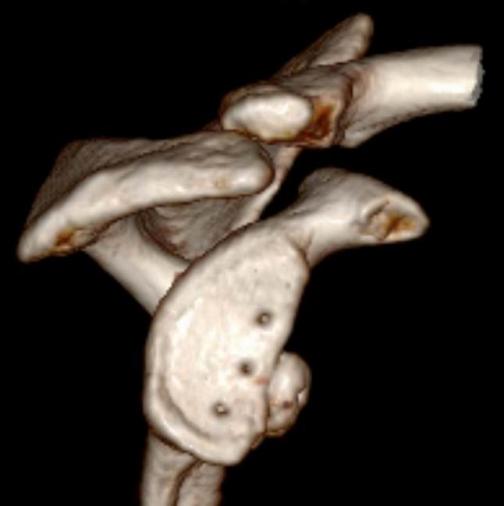

肩关节Bony-Bankart损伤

肩关节镜下缝合修复Bony-Bankart术后

全镜下Bristow手术

在国际上首创关节镜下改良“嵌入式”喙突移位(Bristow)手术,并将其命名为CUIstow手术(Chinese Unique Inlay Bristow)